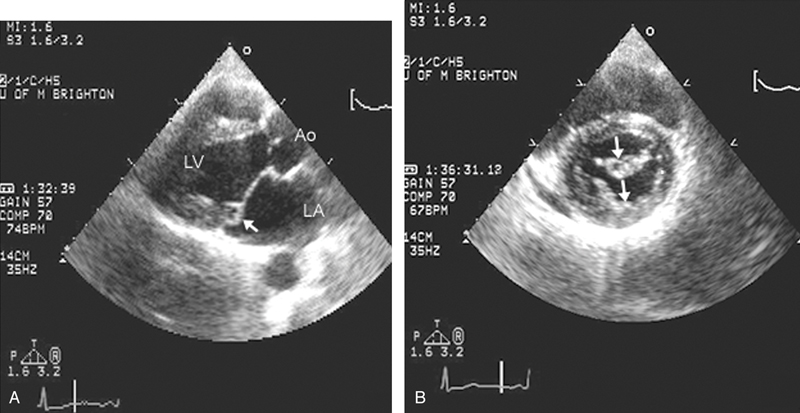

فحوصات تشخيصية لبعض امراض القلب والشرايين التاجية